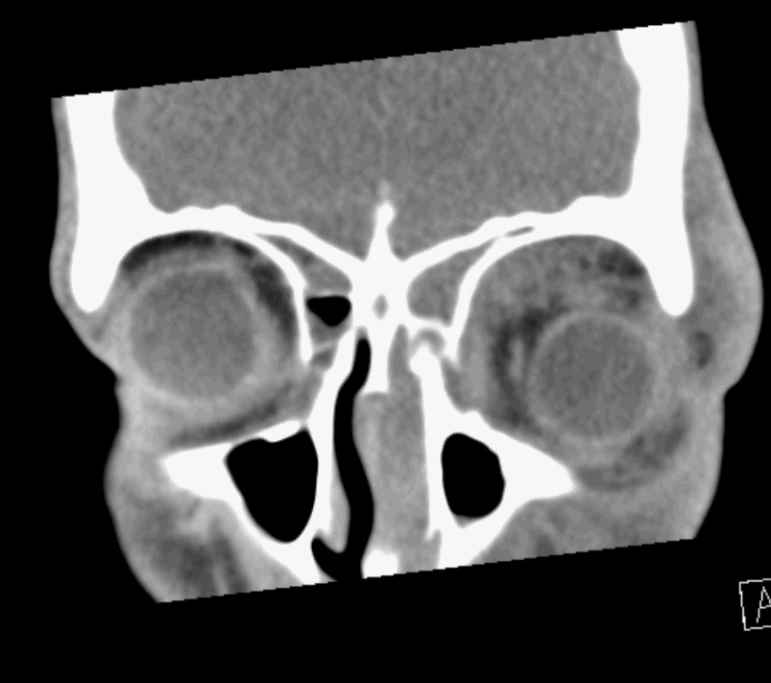

The cruise ship docked at a port in New Zealand the next morning and the patient was transferred to a tertiary hospital. Initial assessment showed he had no light perception in the affected eye and his pupil appeared dilated and not responsive to light stimuli. The hospital emergency department organised an urgent computed tomography (CT) scan of the orbit and head which showed a left-sided orbital cellulitis with sub-periosteal abscess on the medial wall of the orbit with significant obstructive sinus disease (see Fig 2).

Fig 2. Left-sided MRSA-associated orbital cellulitis in a 15-year-old male. CT scan of the orbit in (A) coronal section and (B) axial section, and (C) D) MRI scan of the orbit in coronal section